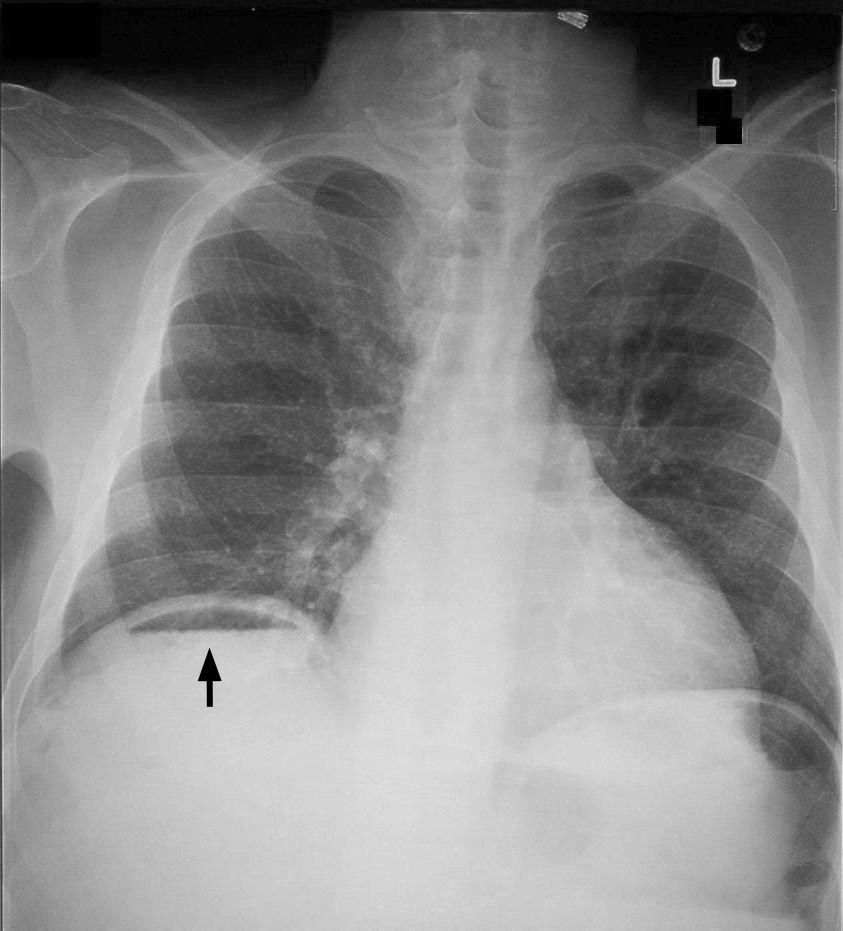

Free air under the diaphragm is known as pneumoperitoneum. Following conditions may give rise to free air under the diaphragm: - perforation of hollow viscus - post laparotomy - pneumatosis coli - vaginal insufflation to determine tubal patency - Chilaiditi's syndrome - biliary lipomatosis - liver abscess rupture - air in retroperitoneum - incompetent sphincter of Oddi - gallstone ileus - post-tonsillectomy - post dental extraction - intra-abdominal sepsis - arthroscopy of knee Reference: https://www.ncbi.nlm.nih.gov/pmc/articles/PMC5079354/ Image via: https://en.wikipedia.org/wiki/Pneumoperitoneum